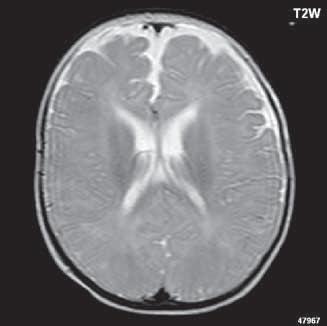

Obr. I.1.1f Rozšířené subarachnoidální prostory (věk 6 měsíců – v tomto období se nejedná o patologický stav, ale jsou fyziologicky prostornější)

Obr. I.1.1g Rozšířené subarachnoidální prostory (věk 6 měsíců – v tomto období se nejedná o patologický stav, ale jsou fyziologicky prostornější); stejný pacient jako na obr I 1 1f

f g h ch

Obr. I.1.1h Fyziologický nález, již normální šíře subarachnoidálních prostor (věk 1,5 roku); stejný pacient jako na obr I 1 1f, g

Obr. I.1.1ch Fyziologický nález, již normální šíře subarachnoidálních prostor (věk 1,5 roku); stejný pacient jako na obr I 1 1f, g, h